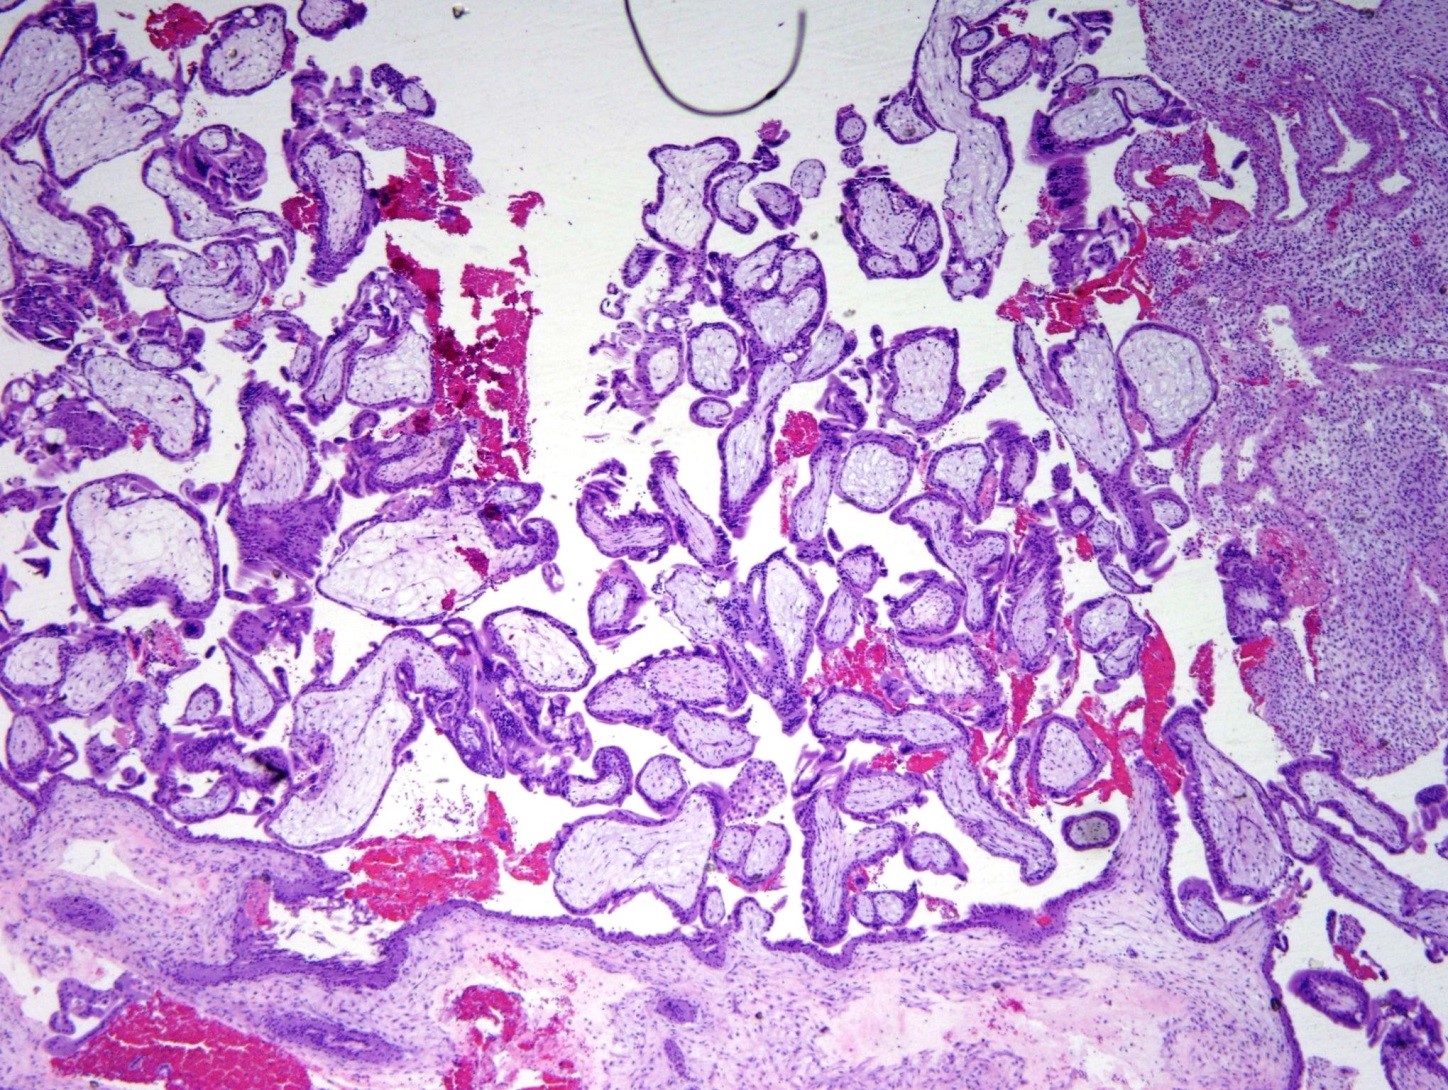

Products of Conception

FIRST SEMESTER PRODUCTS OF CONCEPTION: Grossly small amount of tissue (tissue minus blood <4 -5cm). Villi are small (size of 2-2.5 endometrial glands or <4 mm) (figure 1). Trophoblastic proliferation in polarized (trophoblasts grow in columns towards the oxygen source) Exceptions: extrauterine (fallopian tube pregnancy) can show significant trophoblastic proliferation. This can be attributed toContinue reading “Products of Conception”